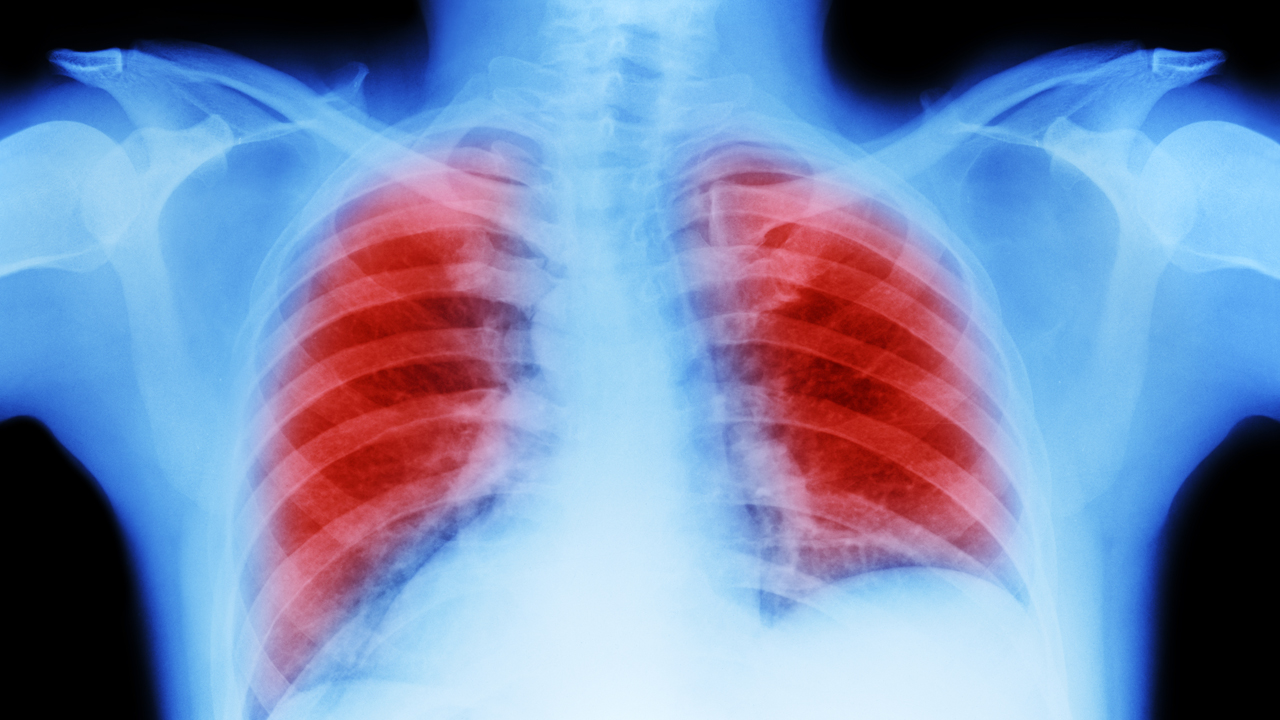

Should You Consider Lung Cancer Screening?

Depending on your age, cancer screening should be part of your preventive care. For people with a family history of cancer, earlier and more frequent cancer screenings may be recommended. You may be familiar with a Pap test for cervical cancer, a mammogram for breast cancer, a PSA test for prostate cancer and a colonoscopy for colorectal cancer. For people with a personal history of smoking, lung cancer screening is now strongly recommended as a way to detect cancer early, when it is easiest to treat.

According to American Cancer Society, lung cancer is the leading cause of cancer-related death in the United States; it accounts for almost 25% of all cancer deaths.

"Lung cancer can spread silently, and often you'll have no symptoms until it becomes more advanced or has spread to other parts of the body," says Northwestern Medicine Thoracic Imaging Physician Eric M. Hart, MD. "This is why screening for lung cancer is so important if you meet the criteria."

How Lung Cancer Screening Works

A low-dose computerized tomography (low-dose CT) scan looks for any areas of concern, such as nodules, or "spots "in your lungs. Like an X-ray, the scan takes just seconds. For most people, the exam result will be negative — nothing of significant concern will be found. For a small minority of patients, a nodule will be found that may require additional follow-up or further testing. For a very small number of patients, that further testing might include a biopsy, a procedure to remove a tissue sample for analysis by a pathologist.